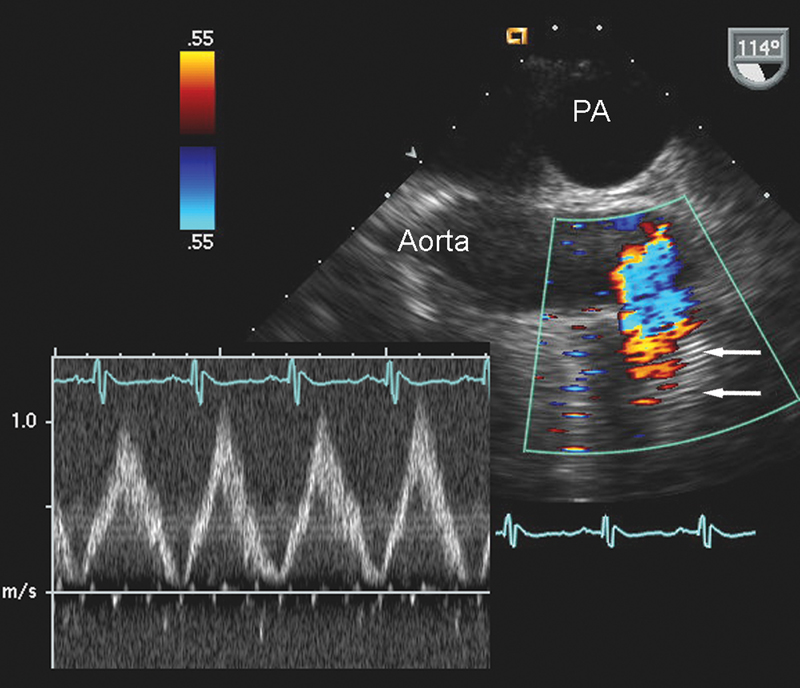

فحوصات تشخيصية لبعض امراض القلب والشرايين التاجية